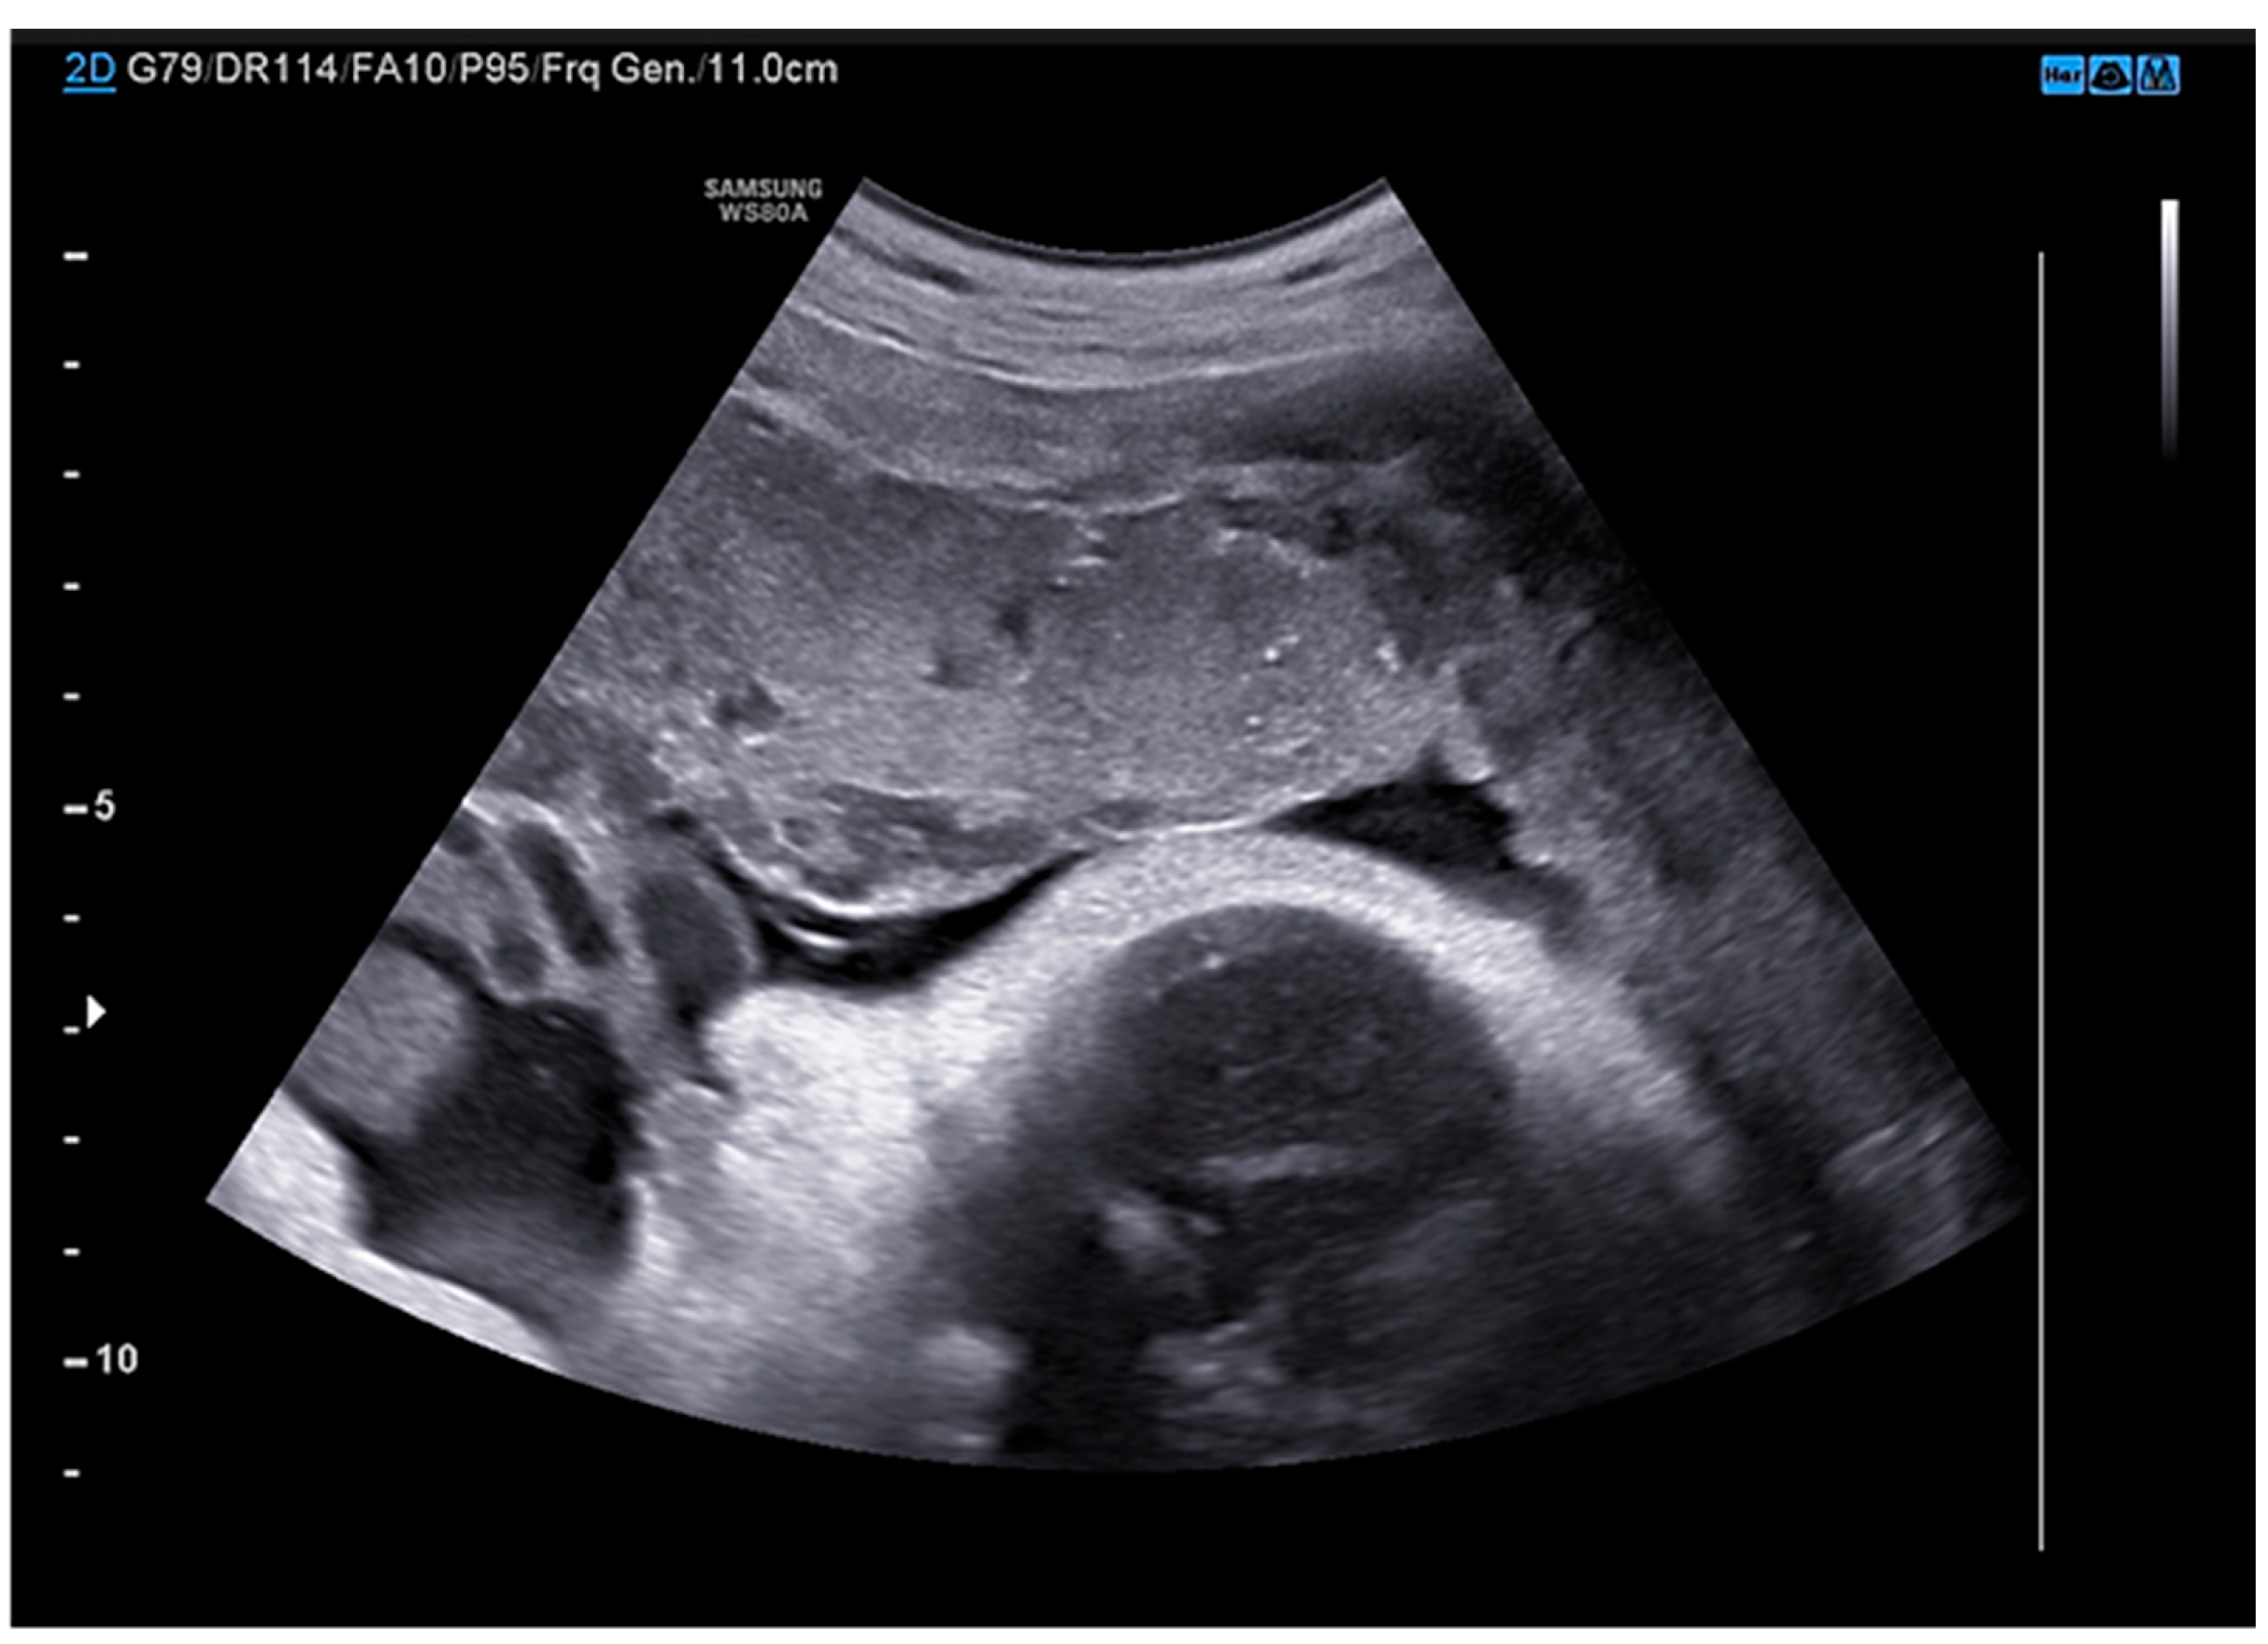

M.G. is a 38 years old woman with two previous pregnancies (G2P2), who was 36 weeks of gestation in her third uneventful pregnancy. All the ultrasound scans (US) performed highlighted a regular fetal growth and normal placental functional markers (umbilical Doppler Pulsatility index), Figure 1 and Figure 2. Her only known risk factor is smoking, which she had temporarily quitted.

Figure 2. Sonogram depicting a normal umbilical doppler Pulsatility Index during the third trimester ultrasound scan.